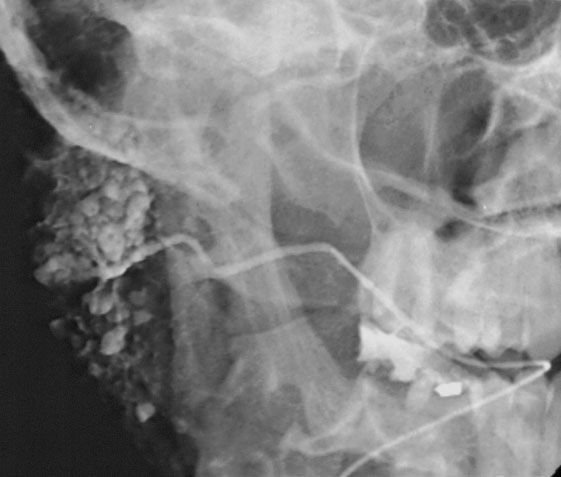

Sialography (also termed radiosialography) is the radiographic examination of the salivary glands. It usually involves the injection of a small amount of contrast medium into the salivary duct of a single gland, followed by routine X-ray projections.